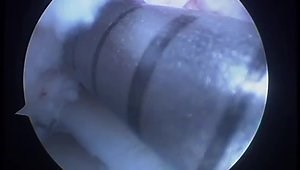

ACL Repair - ACL

Graft Preparation - Hamstring Autograft

Surgical Technique Animation - Hamstring ACL